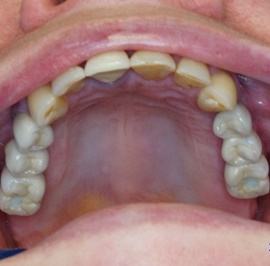

Implantacja natychmiastowa. Zęby paradontyczne. Usuniete zgodnie z popularną obecnie na zachodzie techniką: usuń zęby zanim zaniknie kość. Wynikiem takiego postępowania jest mniejsza trauma dla pacjenta i krótszy okres trwania rehabilitacji protetycznej, niższe całkowite koszty leczenia. Ale jednocześnie więcej implantów i mniej własnych zębów. W długotrwałym okresie obserwacji takie podejście daje dobre wyniki.

Pacjent z długą historią leczenia implantologicznego. Pierwsze implanty w pozycjach 23, 24 miał wkręcane w Warszawie przed 25 laty. Implant w pozycji górnego prawego kła ma agresywny gwint, ponieważ bezpośrednio po implantacji był obciążony (immediate loading) tymczasowym atachmentem ball abutmentv do stabilizacji tymczasowej protezy ruchomej. Kość szczęki regenerowana i odbudowywana etapami w całym górnym prawym kwadrancie. Pacjent planuje uzupełnić brakujące zęby 25, 26.